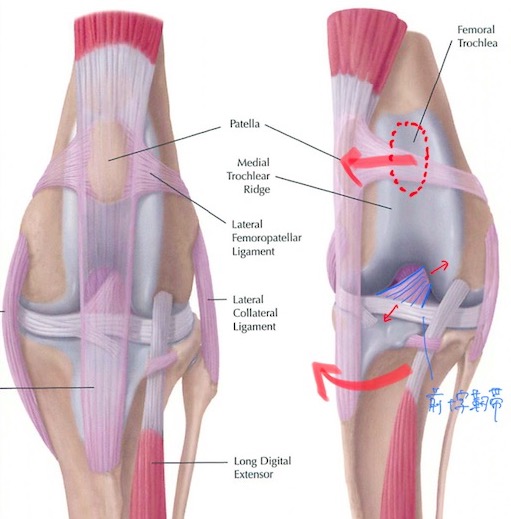

膝蓋骨(膝のお皿の骨)の内側への脱臼は犬(特に小型犬)で最も多く見られる整形外科疾患の1つであり、その多くは生まれ持っての解剖学的な問題による先天性のものです。稀ではありますが猫でも見られます。

また、膝蓋骨の脱臼が慢性的に起こっている膝関節では関節が内側に引っ張られる力がかかっているため、膝の中の靭帯(前十字靭帯)に負荷がかかっており、年齢を重ねるにつれてダメージが蓄積し、将来的に靭帯の断裂を招いてしまうリスクも考えなければいけません。(赤矢印)

X線を見ると、膝蓋骨が本来あるべき位置(赤点線)から内側に脱臼してしまっていることが分かります。(黄色)

整形外科学的検査とX線検査により、左右共に膝蓋骨内方脱臼のGrade3と診断しました。